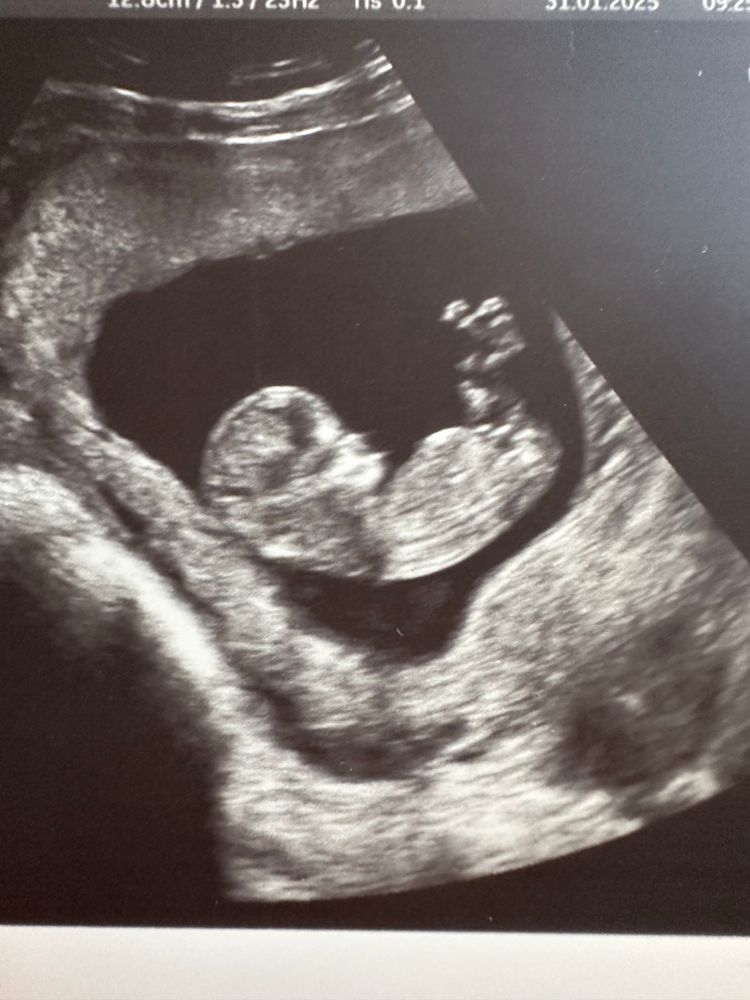

Похож на ребёнка 😊 На фото ножками закрылся. Предположение узиста у меня совпало.

Полового бугорка не видно, везде ножки наверх подняты. Но по форме головки, мне кажется, девочка